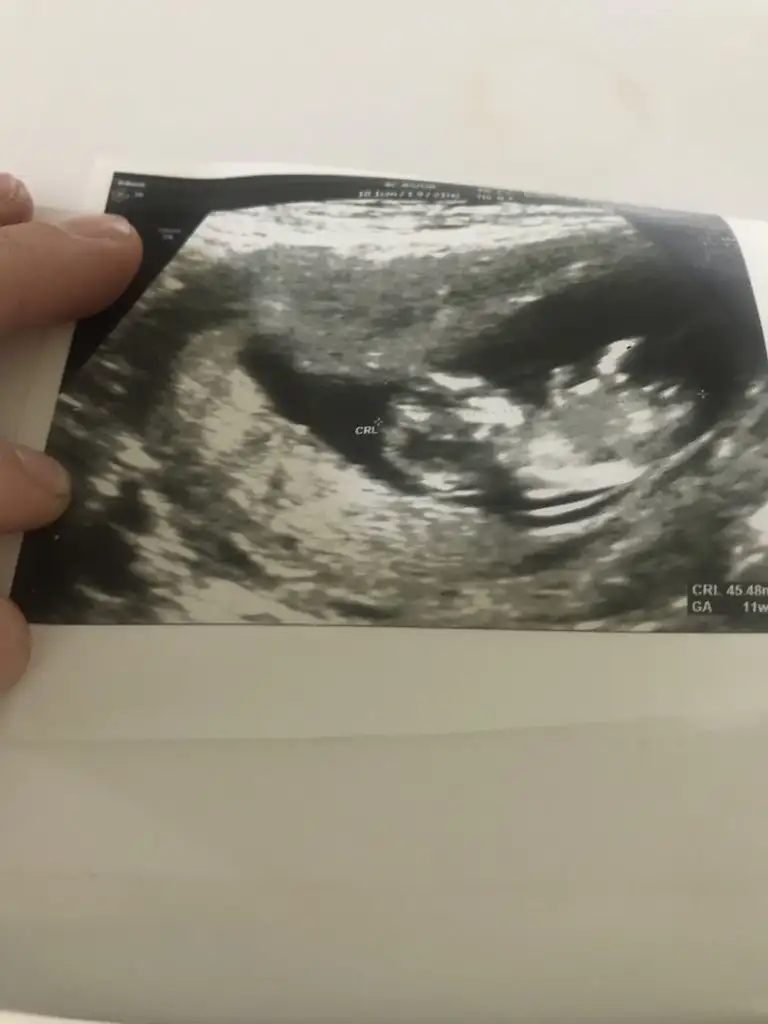

Merhabalar; 11+3 karından ultrason. İsterseniz 7 nci hafta görüntüsü de verebilirim

Eklentiler

• D987DFD0-19AF-4ACB-B063-D4568A92148D.webp

D987DFD0-19AF-4ACB-B063-D4568A92148D.webp

16,3 KB · Görüntüleme: 103